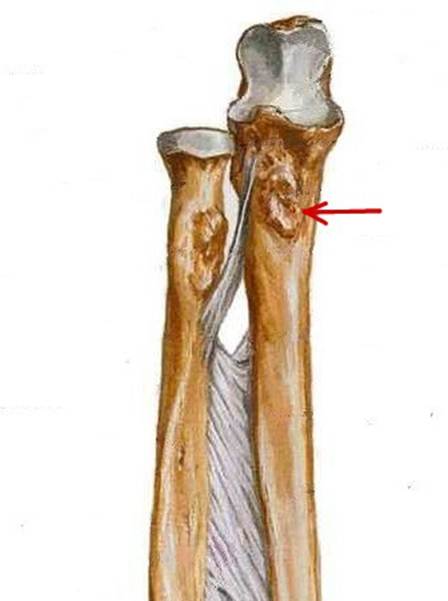

S: Стрелка указывает на caput ulnae (латинский язык).

S: Стрелка указывает на шиловидный отростой локтевой кости.

S: Стрелка указывает на венечный отросток локтевой кости.

S: Стрелка указывает на tuberositas ulnae (латинский язык).

S: Стрелка указывает на tuberositas ulnae